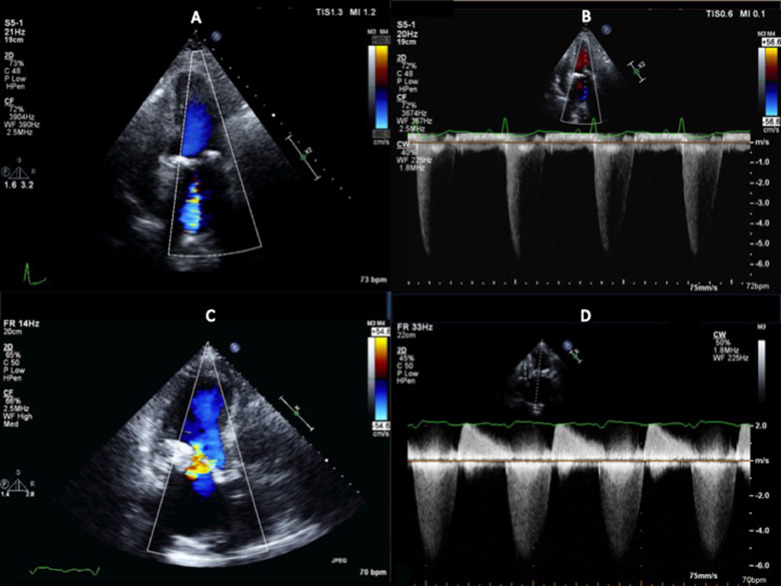

2D ECHO:

- Color flow imaging, CW Doppler. Color Doppler allows for detection of the presence of MR and separates mild regurgitation from moderate to severe disease. Shape and direction of the jet is helpful.

- Dilation of LV and mitral annulus results in central, symmetric regurgitant jet.

- PLAX, PSAX, A4 and A3 aka long axis are useful

- Central jet w/area less than 4 cm2 or less than 20% of the LA area in a nonoblique view is – mild MR.

- CW Doppler spectral recording – shows rapid increase in velocity in isovolumetric contraction (proportional to the rate of rise in LV pressure of dP/dt) from baseline to a max velocity of 5 to 6 m/s. Velocity stays high throughout the systole. During ISVR – the velocity rapidly returns to baseline.

Vena Contracta:

- Diameter should be measured if color Doppler imaging shows an eccentric or large jet or if CW Doppler suggests more than mild MR.

- Mild MR: VC is visualized in PLAX or PSAX, Apical views may be used If those other 2 aren’t visualized.

PROXIMAL ISOVELOCITY SURFACE AREA – PISA

Measurements requirements:

- A4C or PLAX

- Narrow sector width

- Zoom mode

- Aliasing velocity set at 30 to 40 cm/s in the direction of blood flow

- Simulation 2D imaging to show leaflet closure plane

- Radius measured from aliasing velocity to valve closure plane

- Underestimation of regurgitation – PISA occurs flattened

PISA = 2 x pi x r2 Regurgitant flow= 2 x pi x r2 x Va (Aliasing velocity at radial distance)